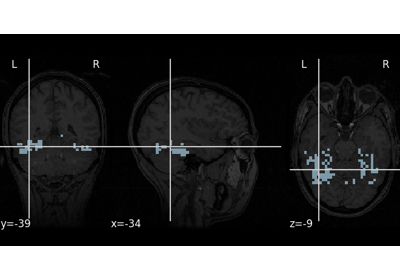

Interactive html viewer of a statistical map, with optional background.

Examples using nilearn.plotting.view_img

Decoding with ANOVA + SVM: face vs house in the Haxby dataset